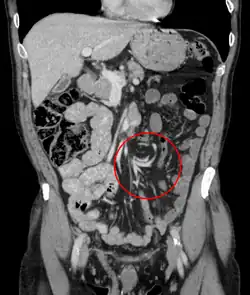

A clínica é típica de abdômen agudo. O diagnóstico normalmente é feito com Raio-X (parece um balão radiolúcido ou com grãos de café) e tomografia computadorizada.

Diagnósticos diferenciais incluem as causas mais comuns de obstrução intestinal mecânica: diverticulite, adenocarcinoma de cólon, doenças inflamatórias intestinais (Colite ulcerosa e Crohn)